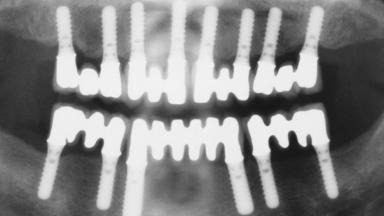

Immediate Loading of Eight Implants in the Maxilla and Six Implants in the Mandible and Final Restoration with Three-Unit and Four-Unit FDPs

# of Implants 14

Type of Implants One-Piece

Defining Characteristics Fully edentulous upper jaw to be rehabilitated with four or more implants

Modality 6+ implants with immediate loading

Loading Protocol Immediate